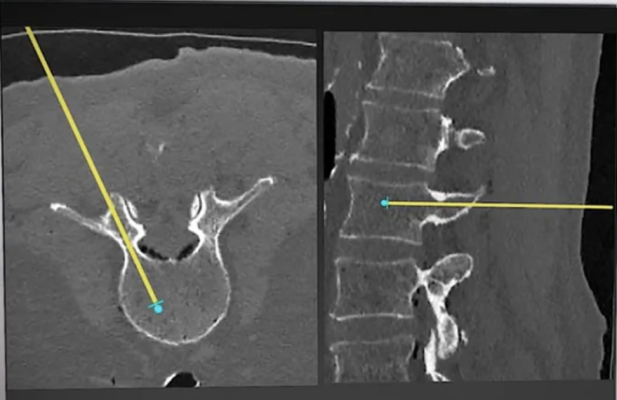

The Vuze System is a software solution installed on an off-the-shelf PC. It operates with unmodified surgical tools, uses no markers, references or cameras, and makes 3D imaging in the operating room (OR) entirely optional. Using proprietary image processing algorithms, it overlays in real time graphical representations of standard surgical tools seen in intra-operative 2D X-ray images onto axial and sagittal cross-sections that it generates from the patient’s standard pre-operative 3D scan. The Vuze System received its initial U.S. FDA 510(k) clearance in 2022 and completed a first-in-human clinical trial in 2023.